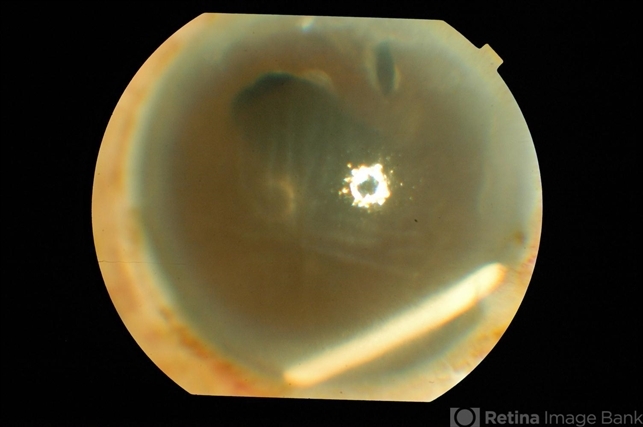

- Ozurdex Implant migration into AC

- Right eye of an elderly male was treated with intravitreal Ozurdex implant for postoperative cystoid macular edema (not responding to intravitreal triamcinolone acetonide). 4 weeks post-injection the implant is found in the AC with severe corneal edema likely from mechanical trauma to the corneal endothelium.